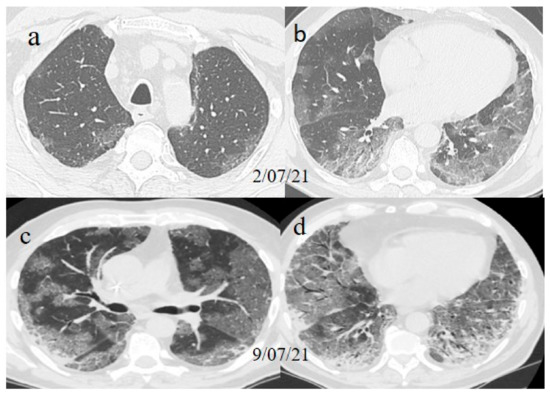

A chest Computed tomography (CT) performed in the emergency department showed a typical central and peripheral distribution of ground-glass opacity (GGO) COVID-19 pneumonia. The CT-SS score showed a value of 13/20

One week later (on 9 July), another chest CT was performed due to the worsening of the patient’s symptoms with SO2 at 76% and PO2/FiO2 190.

The chest CT showed extended pneumonia, with an evolution in a crazy paving pattern and consolidation areas (CT-SS 16/20). The patient died 5 days later.